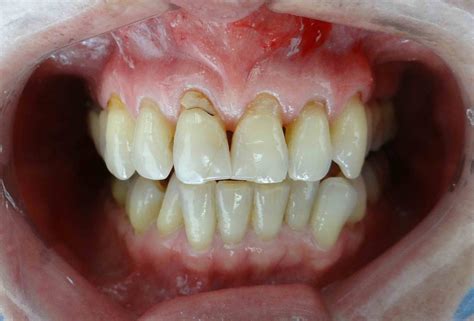

Un paciente con retracción gingival, es aquel que ha perdido una parte de la encía dejando la raíz del diente al descubierto. El primer signo de esta condición es observar que las encías se retraen dejando al descubierto la raíz del diente y creando un efecto estético de dientes demasiado largos.

Una encía sana debe tener un aspecto brillante, no sangrar y cubrir una parte de los dientes, protegiéndolos. Cuando hay recesión gingival, se descubre lo que suele estar oculto.

El cuello es la zona que se encuentra entre la corona y la raíz y resulta muy sensible a los estímulos táctiles, químicos o térmicos. Si al tomar un helado sientes dolor, es posible que sea a causa de la exposición de los cuellos en algunas piezas. En los casos más severos también es visible la raíz.

Si tienes las encías retraídas seguro que te has dado cuenta rápidamente. Solo con sonreír podrás notar cómo tus encías muestran más diente del que debieran. No obstante, el proceso de pérdida de tejido es paulatino.

- Estética: Las encías comienzan a reducirse, permitiendo que el diente quede más expuesto. A veces las raíces dentales se hacen muy visibles.